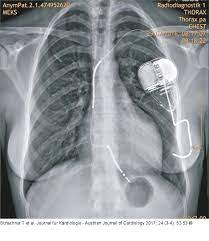

Icd Röntgen - Spondylodiszitis Wikipedia : We would like to show you a description here but the site won't allow us.. Man nutzt sie beispielsweise zur diagnostik von knochenbrüchen, aber auch von krankheiten des brustraums (wie lungenentzündung, vergrößerung des herzmuskels bei herzschwäche, aussackungen der aorta) oder bauchraums (wie darmverschluss, gallensteine). Die untersuchung kann bei der diagnose einer vielzahl von erkrankungen helfen und kommt dementsprechend oft zum einsatz. Zacken, erhebungen oder randwülste) darstellen. Aug 21, 2018 · röntgen des knochensystems zur diagnose von knochenbrüchen, verschleiß, entzündungen und verletzung von gelenken, sehnen oder bändern röntgenuntersuchungen des kopfes zur feststellung von schädelbrüchen und entzündungen der nasennebenhöhlen. Darunter versteht man die einfachste art einer röntgenuntersuchung.

Darunter versteht man die einfachste art einer röntgenuntersuchung. Atelektazi, akciğerin bir kısmının ya da akciğerlerden birinin tamamen büzüşmesi sonucu yeterince genişleyememesi ve böylece işlevini yitirmesidir.atelektazi durumunda daha az hava içeren akciğer parankimi oluşur. Aug 21, 2018 · röntgen des knochensystems zur diagnose von knochenbrüchen, verschleiß, entzündungen und verletzung von gelenken, sehnen oder bändern röntgenuntersuchungen des kopfes zur feststellung von schädelbrüchen und entzündungen der nasennebenhöhlen. Spondylosis deformans, deutsch spondylose (auch wirbelsäulenverschleiß genannt), ist ein sammelbegriff für degenerative veränderungen an wirbelkörpern (und intervertebralräumen), die sich röntgenologisch als unregelmäßigkeiten (z. We would like to show you a description here but the site won't allow us. Man nutzt sie beispielsweise zur diagnostik von knochenbrüchen, aber auch von krankheiten des brustraums (wie lungenentzündung, vergrößerung des herzmuskels bei herzschwäche, aussackungen der aorta) oder bauchraums (wie darmverschluss, gallensteine). Zacken, erhebungen oder randwülste) darstellen. Die untersuchung kann bei der diagnose einer vielzahl von erkrankungen helfen und kommt dementsprechend oft zum einsatz.